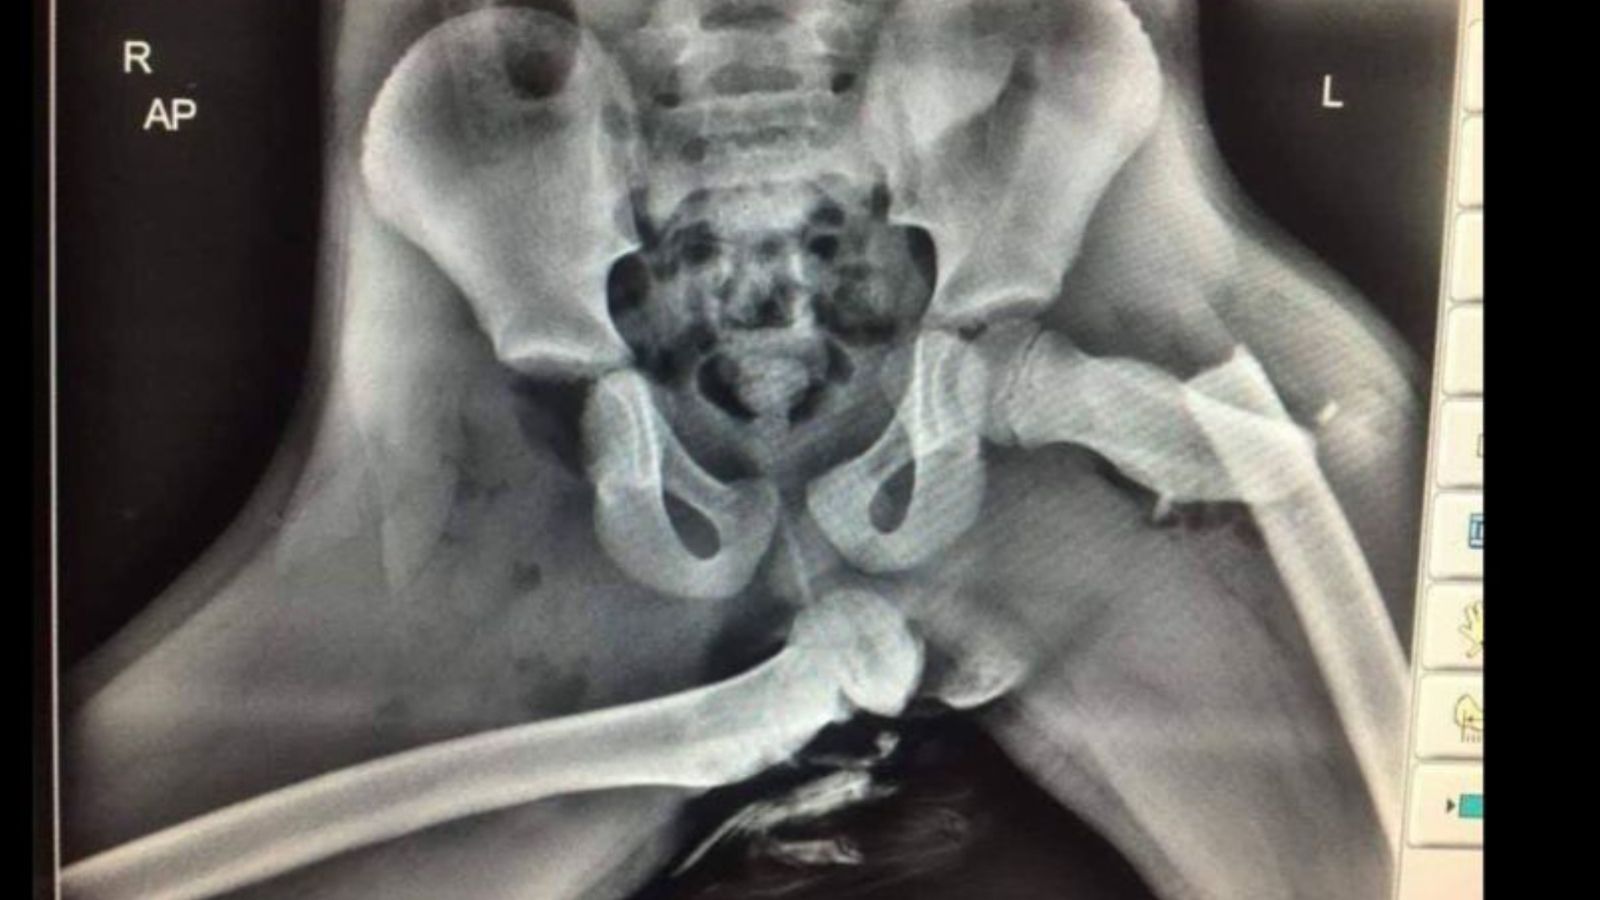

Para concientizar al público en general, ya que la imagen fue publicada en Twitter, la policía del distrito de Dyfed-Powys en Gales compartió esta imagen que pertenece a una radiografía de una víctima de un siniestro automovilístico.

Allí se puede ver la rotura de distintos huesos de la pierna como el fémur, causado justamente por tener colocado los pies en el tablero. Al parecer, en pleno accidente se accionó el airbag y esto hizo de prensa hacia las frágiles piernas de un niño menor de edad.

“Aquí hay una radiografía de horribles lesiones sufridas al pasajero del asiento delantero que tenía los pies en el tablero de instrumentos en el momento de una colisión. Si ve que su pasajero lo hace, deje de conducir y muéstrele esto”, describió en redes sociales uno de los oficiales de policía.